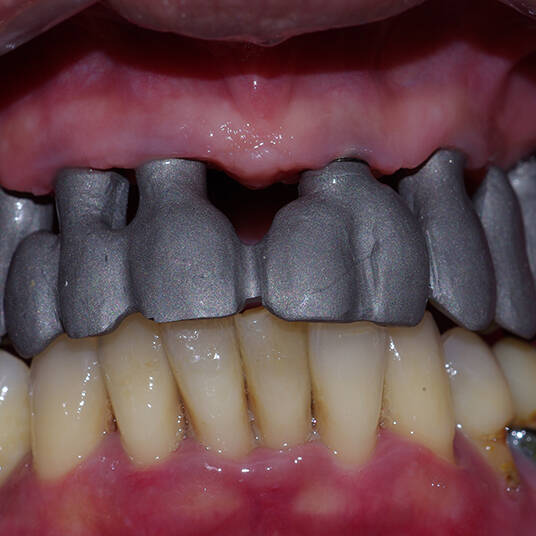

Utilizamos a tecnologia CAD CAM, um sistema avançado que possibilita a confecção precisa das próteses dentárias diretamente sobre os implantes. Esse método inovador garante um ajuste perfeito, um resultado estético superior e proporciona muito mais conforto e durabilidade. Com o CAD CAM, nossos pacientes contam com um processo mais rápido e previsível para alcançar o sorriso desejado.